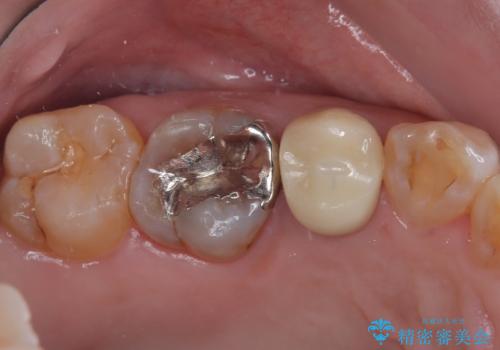

- 笑うときに目立つ銀歯を白くしたいとのことで来院された患者様です。

奥歯ではありますが、以前抜歯矯正をされているので前の方へ移動しており、非常に目立っていました。

仮歯に替えた上で、速やかにオールセラミッククラウンにて補綴治療を行うこととしました。

銀歯を外したところ、土台にほとんどむし歯はなかったため、土台のやり替えを行うことなく、セラミッククラウンを装着しました。